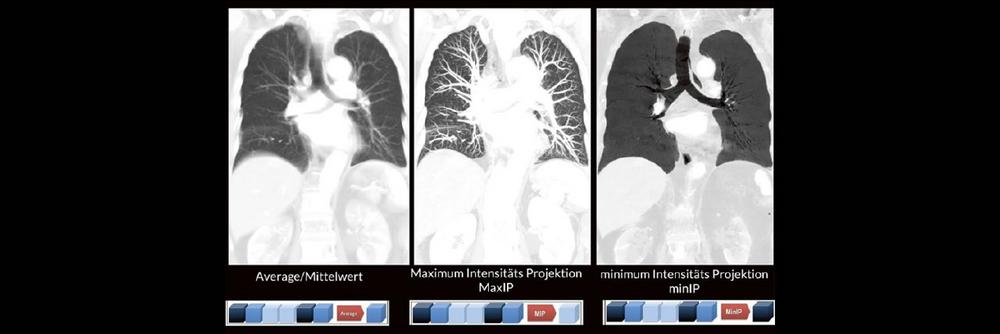

Darüber hinaus werden die unterschiedlichen MPR-Techniken wie z. B. Maximum Intensitäts- Projektionen (MaxIP´s) und minimum Intensitäts Projektionen (minIP´s) oft nicht routinemäßig angewendet. Dabei können verschiedene Pathologien durch den zielgerichteten Einsatz der unterschiedlichen MPR-Techniken oft viel einfacher und besser diagnostiziert werden.

- Maximum Intensität Projektion

- Minimum Intensität Projektion